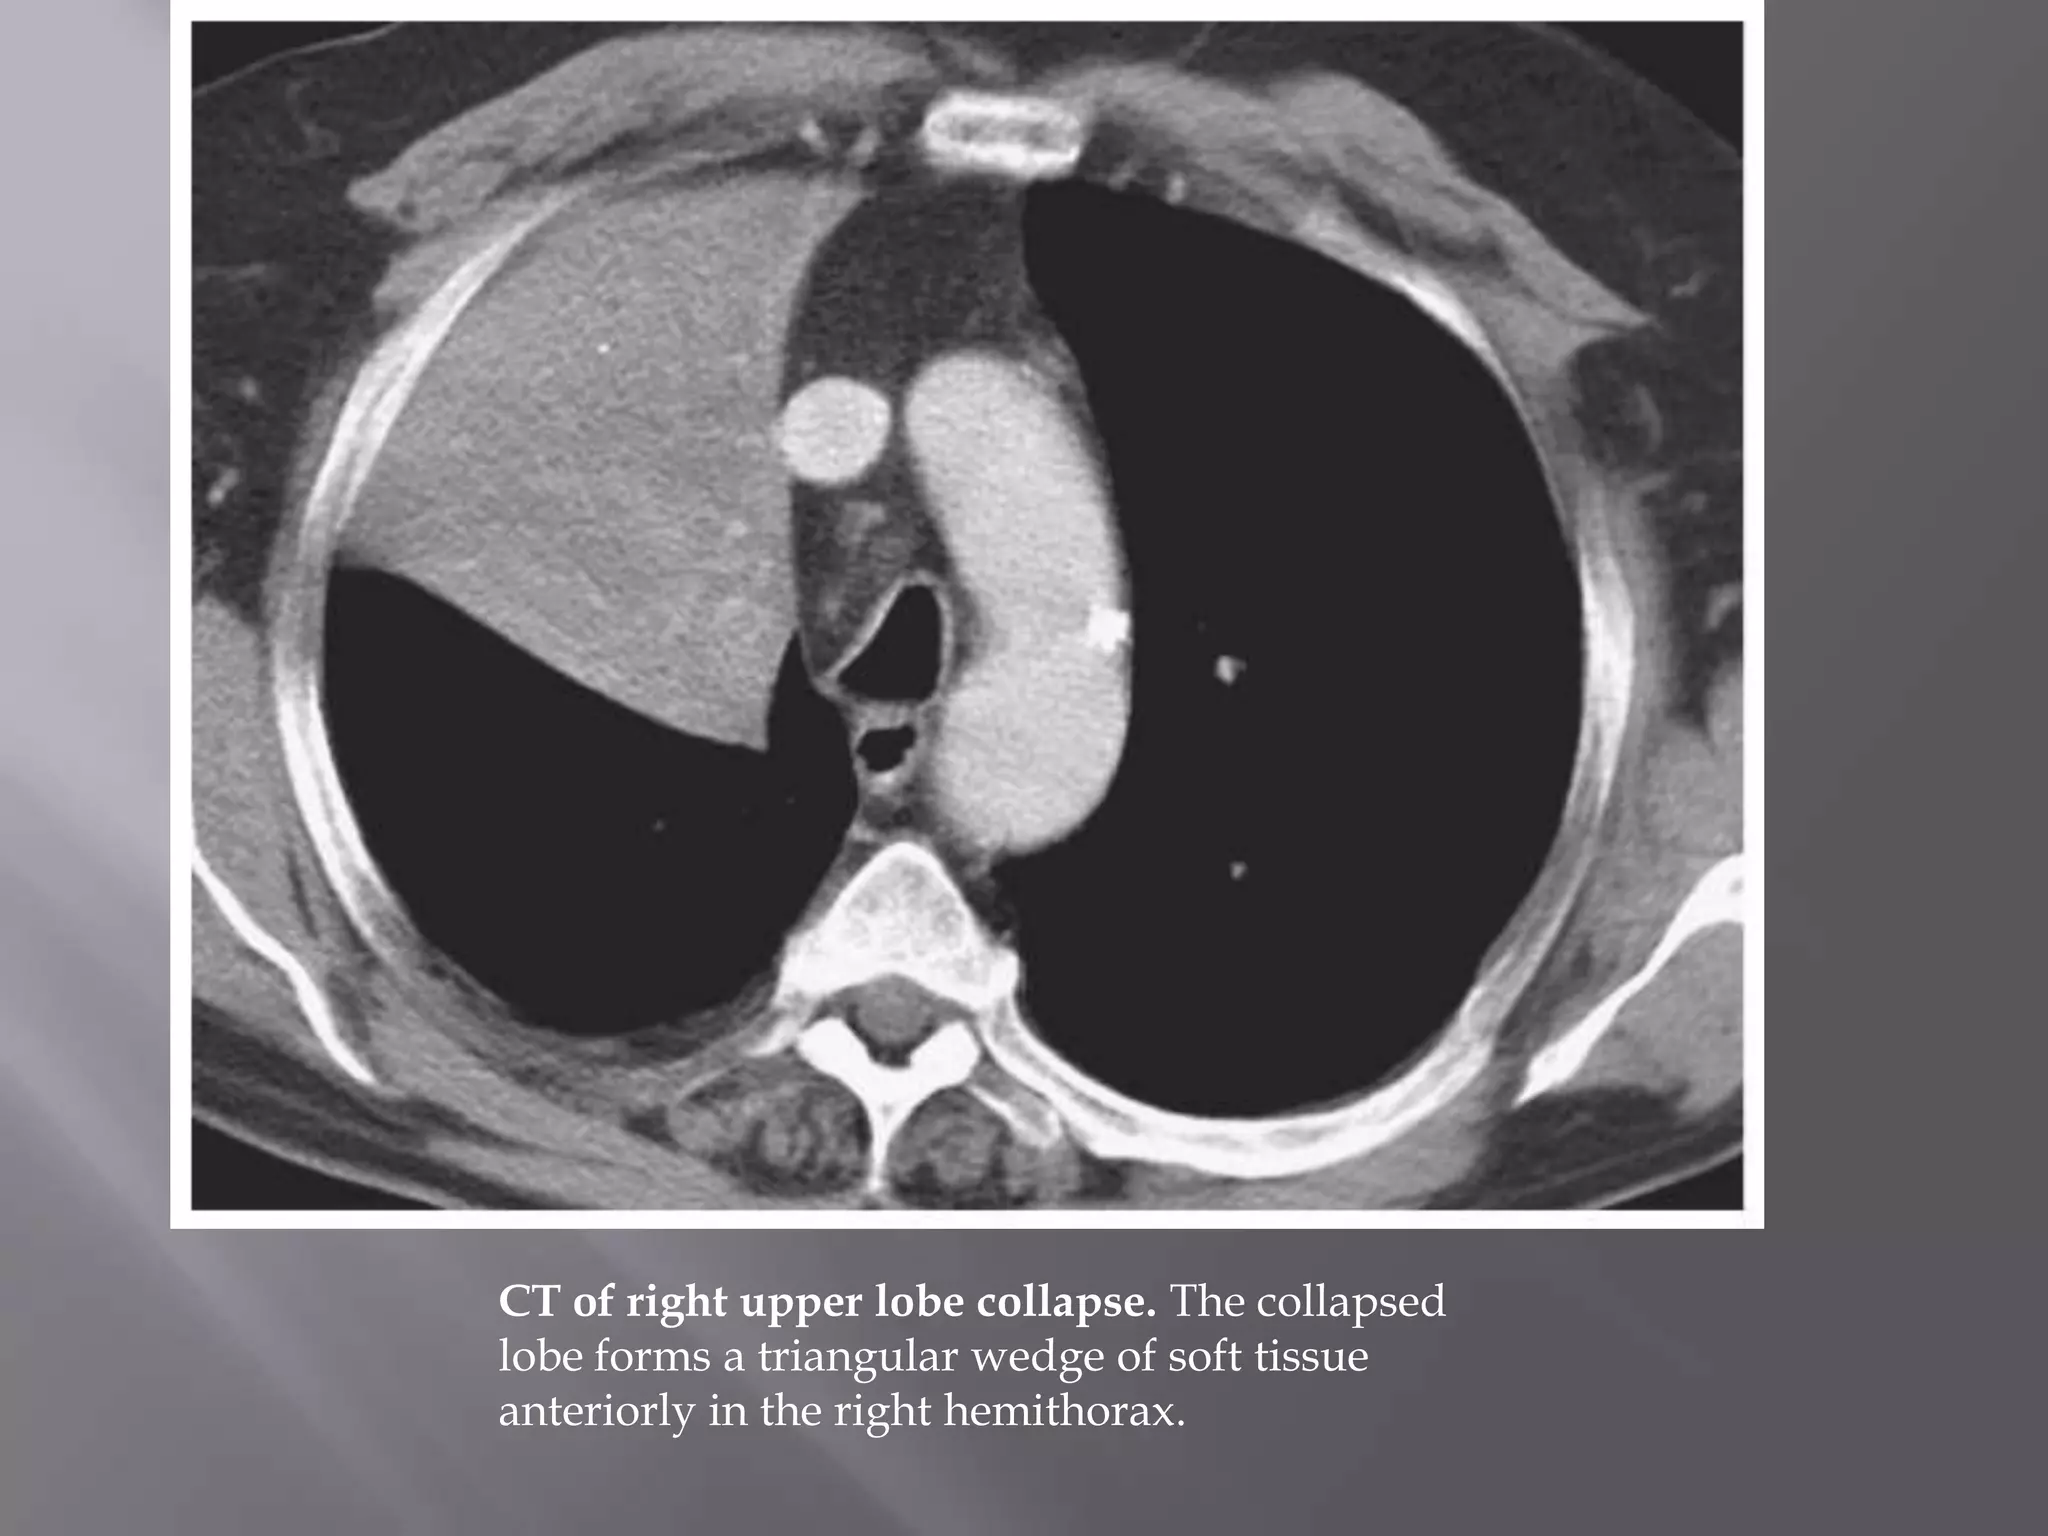

CT of right upper lobe collapse. The collapsed

lobe forms a triangular wedge of soft tissue

anteriorly in the right hemithorax.

CT of rightupper lobe collapse. The collapsed lobe forms a triangular wedge of soft tissue anteriorly in the right hemithorax.